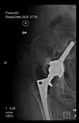

The guiding wire was inserted and controlled with fluoroscopy flashes (Figure 4). The drilling and reaming were carried out in accordance with the recommendations:

Figure 4.

The biocompatible aiming device after insertion of the guiding wire.

In all the cases operated with the above-described targeting procedure, the stems of the cups remained between the cortical bone surfaces without perforation of the linea terminalis, as shown by postoperative radiographs. There were no complicated surgical situations. In 16 cases, the wound healings were uneventful, and the hips were able to bear weight again after postoperative rehabilitation.